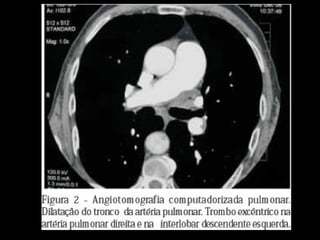

Achados de imagem: Rx e TC

Artérias pulmonares centrais dilatadas;

Trombo ocluindo e reduzindo o diâmetro da artéria

ocluída;

Localização excêntrica dos êmbolos pulmonares

com ou sem calcificações;

Estreitamento abrupto do diâmetro arterial;

Recanalização das falhas de enchimento

intraluminal;

Dilatação das artérias brônquicas.

http://radiographics.rsna.org/content/30/7/1753.full.pdf+html